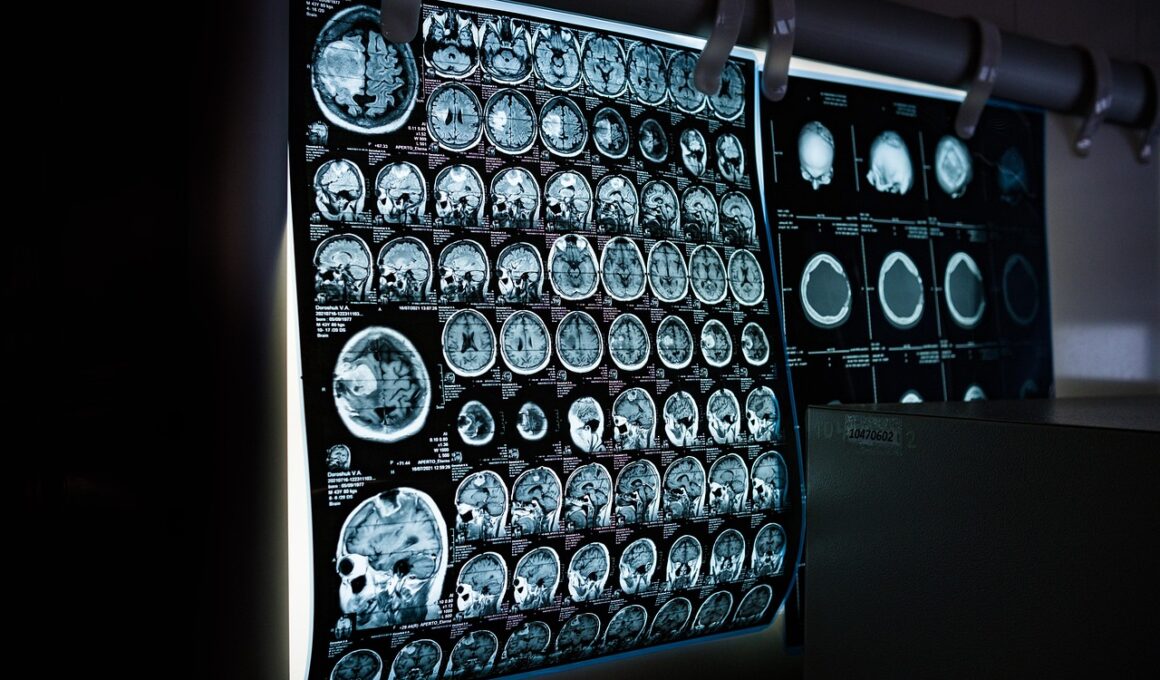

One significant advantage of utilizing 3D imaging is its ability to visualize complex joint structures. In cases of sports injuries, particularly in joints like the knee or shoulder, the intricate anatomy can pose challenges during surgery. By using advanced imaging techniques such as CT or MRI, surgeons can create highly detailed 3D reconstructions of the damaged area. This level of detail allows the surgical team to better understand the injury’s extent and plan a more effective intervention. Moreover, this clarity aids in recognizing potential complications that could arise during surgery. Instead of relying solely on traditional 2D images, the shift to 3D imaging provides a more holistic view. This transformation in visualization helps in the meticulous planning of surgical tactics that can ultimately enhance patient outcomes. Additionally, 3D models can be used for educational purposes, allowing junior surgeons to practice procedures in a simulated environment before performing on actual patients. Leveraging these detailed visuals ensures that surgeons are well-prepared, reducing the chances of intraoperative surprises and increasing the confidence of the surgical team.

The preoperative planning process has been significantly enhanced through the use of 3D imaging. Surgeons can utilize the models generated from these imaging techniques to map out the exact anatomical locations of injuries. This level of precision is essential when considering surgical approaches that may require navigating through critical areas to access the site of injury. With the help of 3D imaging, surgeons can visualize important landmarks, such as nerves and blood vessels, which reduces the risk of damaging these structures during surgery. Furthermore, the ability to rotate and manipulate digital images allows for a better understanding of the spatial relationships within the joint or tissue being treated. Surgical teams can also review these models collaboratively, promoting an interdisciplinary approach that enhances overall surgical strategies. As a result, what is traditionally fraught with uncertainty transforms into a well-defined plan that works in the patient’s favor. This proactive approach allows for a more thorough discussion with patients regarding their procedures and anticipated outcomes. Ultimately, effective preoperative planning facilitates better overall surgical performance.